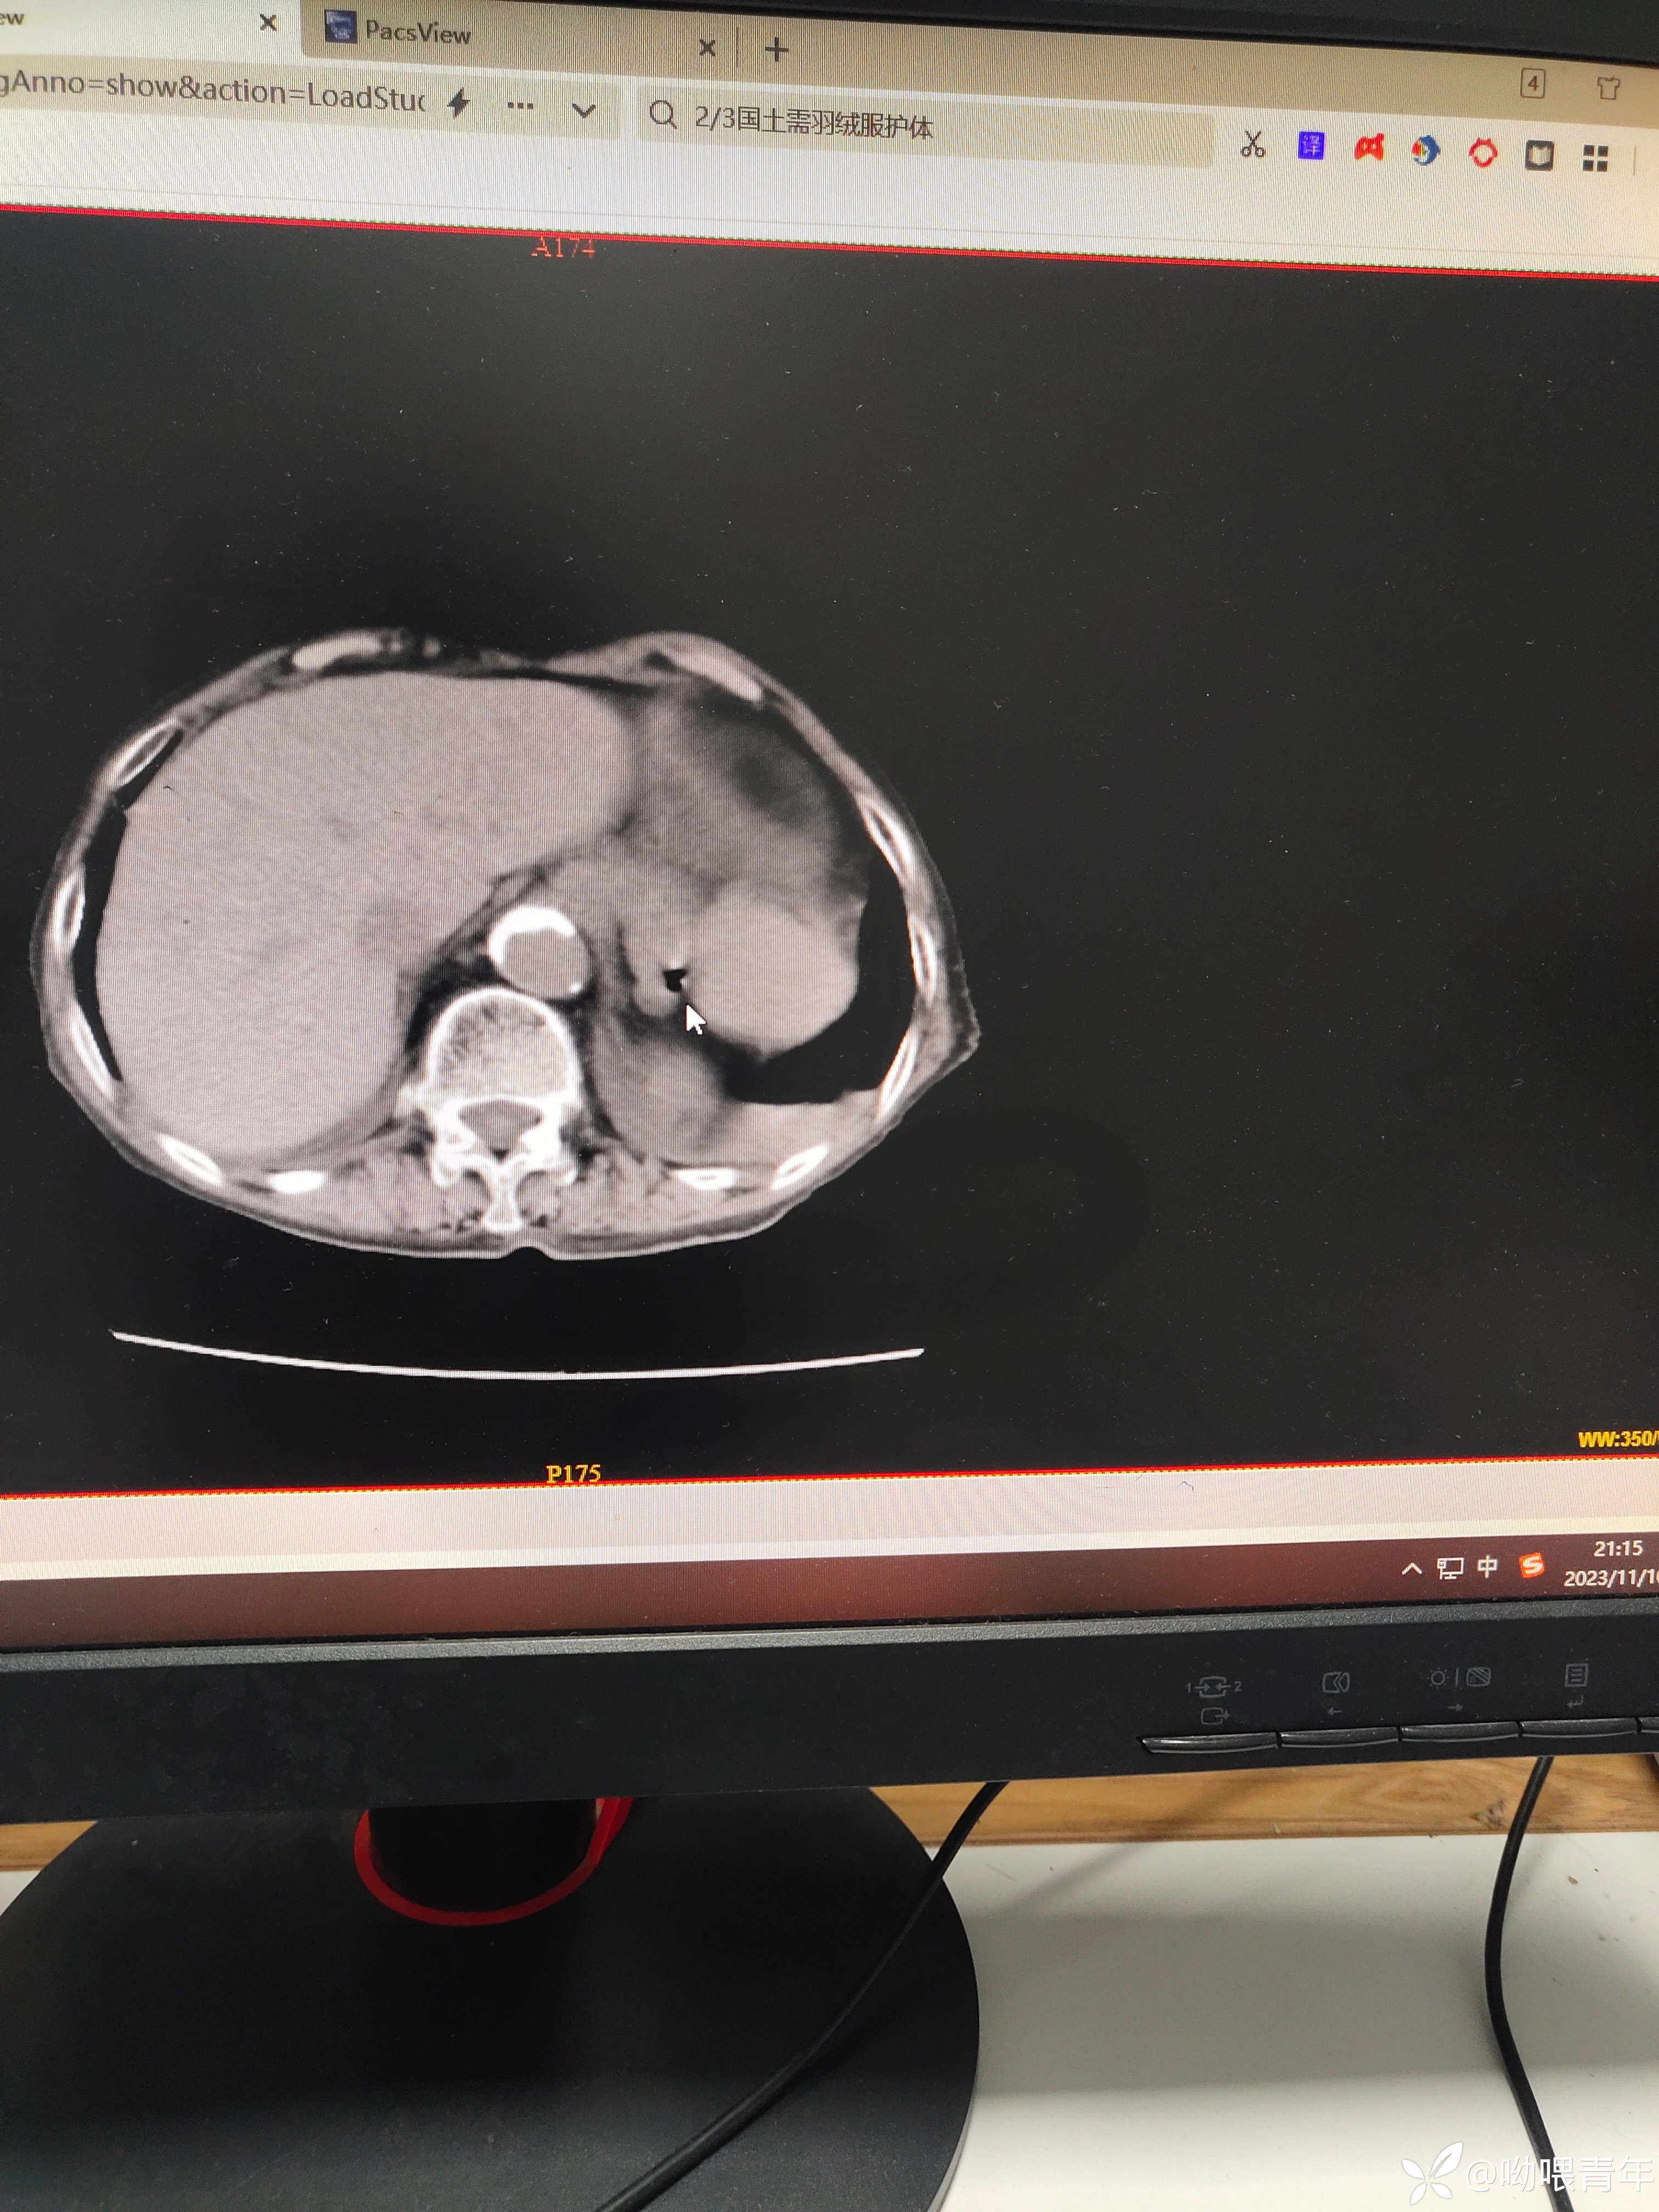

90多岁病人,右腹痛2天急诊入院,行上腹部CT检查提示:1.胆囊形态增大伴泥沙样结石;2.消化道穿孔可能。感染指标正常。查体:体温正常,查体腹肌紧张,右侧腹部轻压痛,无反跳痛。请各位老师帮忙分析一下。